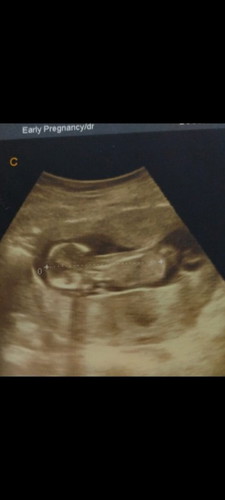

mohon doanya bun biar janinku tetap sehat dan kuat.?

Semoga tuhan slalu melindunginya.amin?